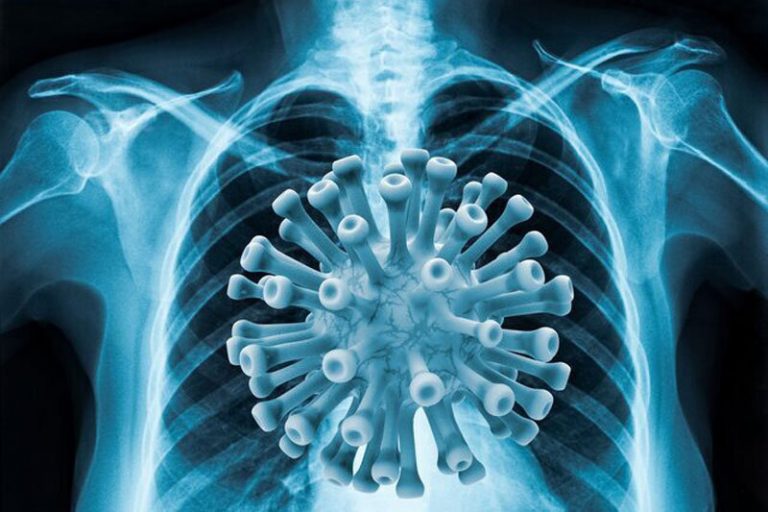

بسیاری از مردم بعد از ابتلا به کرونا به دلیل نگرانی از درگیر شدن ریه اقدام به سی تی اسکن مکرر میکنند و از روز...

در حال حاضر در ایران دو واکسن آسترازنکا و سینوفارم، برای مقابله با کوید19 تزریق میشوند. شاید برای شما هم پیش آمده باشد که بین...